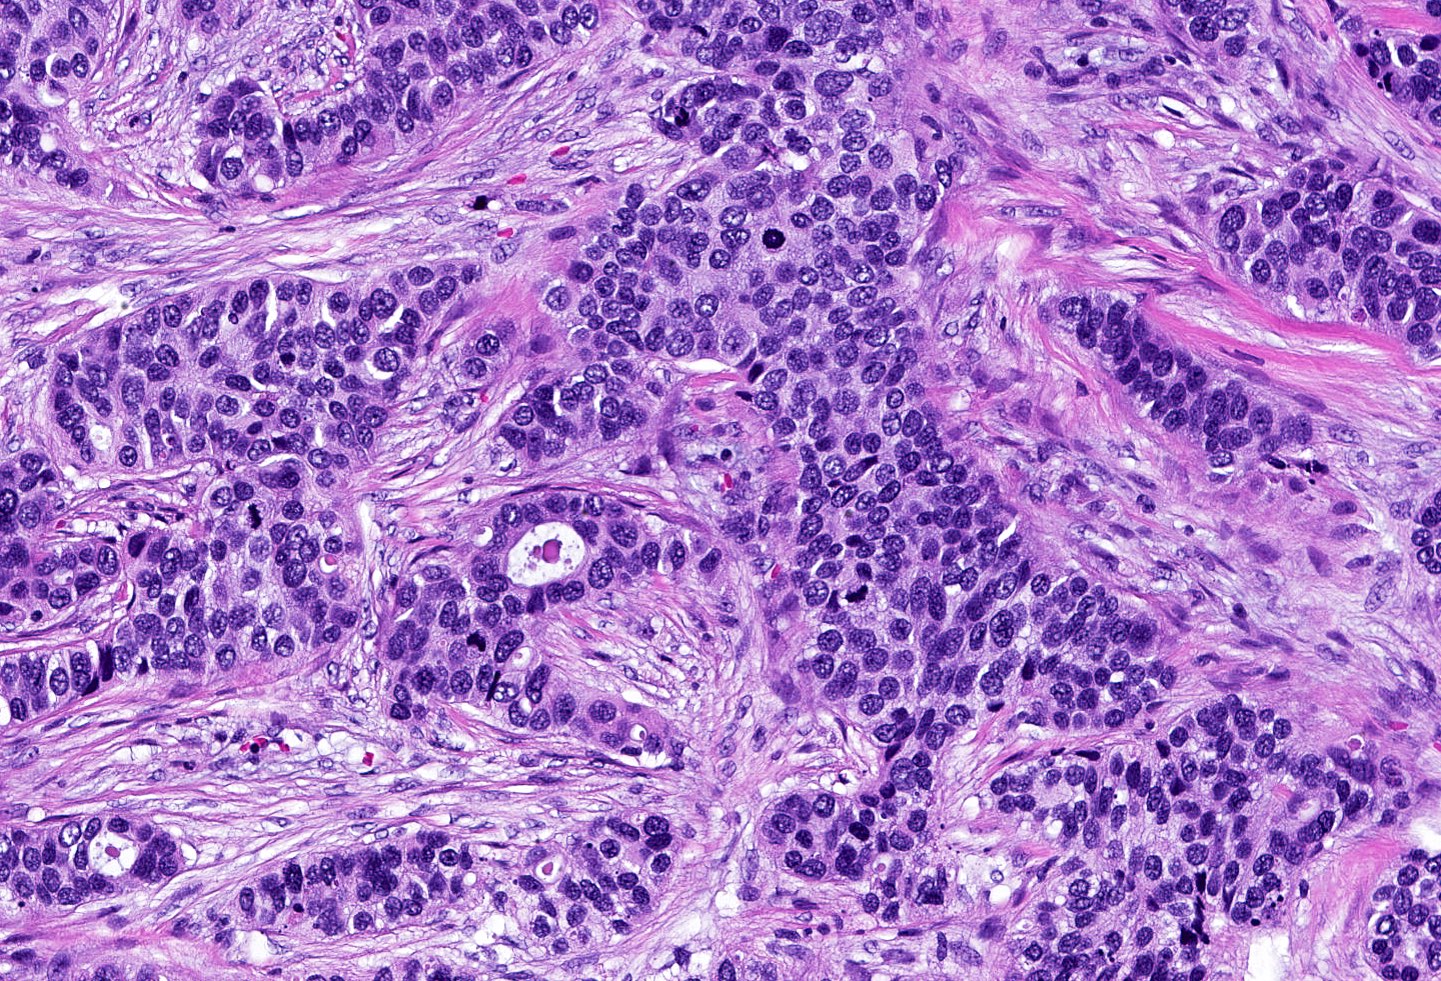

- Triple negative (J Pathol 2008;216:141, Breast Care (Basel) 2020;15:327, Semin Cancer Biol 2021;72:136)

- ER negative, PR negative, HER2 negative, includes high and low grade tumors

- High grade TNBC: IDC, NST grade 3, spindle cell metaplastic breast carcinoma, medullary carcinoma, apocrine carcinoma

- Basal-like: high grade IDC, NST, solid tumor growth with pushing borders, geographic necrosis, nuclear pleomorphism, brisk inflammatory infiltrate, high mitotic index, high Ki67

- Most express basal cytokeratins (keratin 5/6, 14, 17) and EGFR

A 67 year old woman underwent a partial mastectomy for a breast tumor shown in the image. Microscopic sections revealed a high grade invasive ductal carcinoma growing as a solid mass with pushing borders, areas of necrosis, brisk mitoses and abundant tumor infiltrating lymphocytes. The tumor was negative for ER, PR and HER2 and was classified as basal-like by gene expression profiling. What other immunostain(s) might be positive?

B. EGFR. Basal-like breast cancers are typically high grade invasive ductal carcinoma of no special type that show solid tumor growth with pushing borders, geographic necrosis, nuclear pleomorphism, a brisk inflammatory infiltrate, a high mitotic index and a high proliferative index with Ki67. Most basal-like breast cancers express basal cytokeratins (keratin 5/6, 14, 17) and EGFR. Answer A is incorrect because while a minor proportion of triple negative breast cancers can express androgen receptor, the prototypical AR positive breast tumor has apocrine features (apocrine carcinoma). Answer C is incorrect because KIT is not characteristically expressed in breast carcinomas. Answer D is incorrect because synaptophysin may be expressed in breast tumors with neuroendocrine differentiation, which typically cluster within the luminal category.